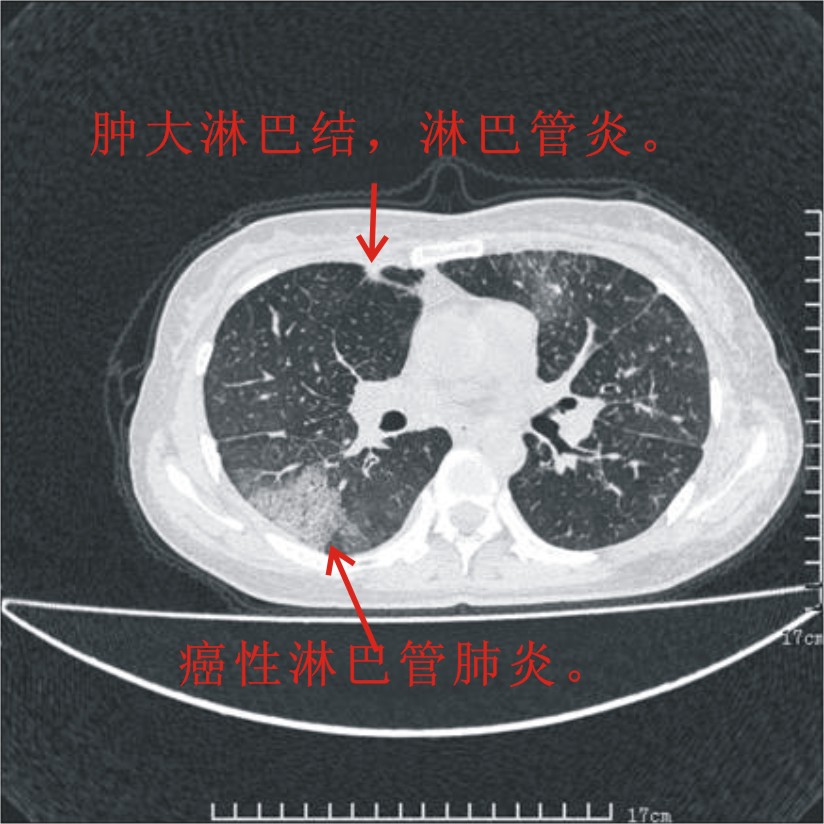

结合病史:认为是典型肺部癌性淋巴管炎、淋巴结转移。请看图解。

肺癌性淋巴管炎征象分为主要征象及合并征象,主要征象包括:

1、近肺门支气管血管周围间质结节状增厚;

2、小叶间隔结节状增厚;

3、小叶中央间质结节状增厚;

4、胸膜下间质结节状增厚。

合并征象为:纵隔淋巴结增大,胸腔积液,肺多发随机分布的小结节等。